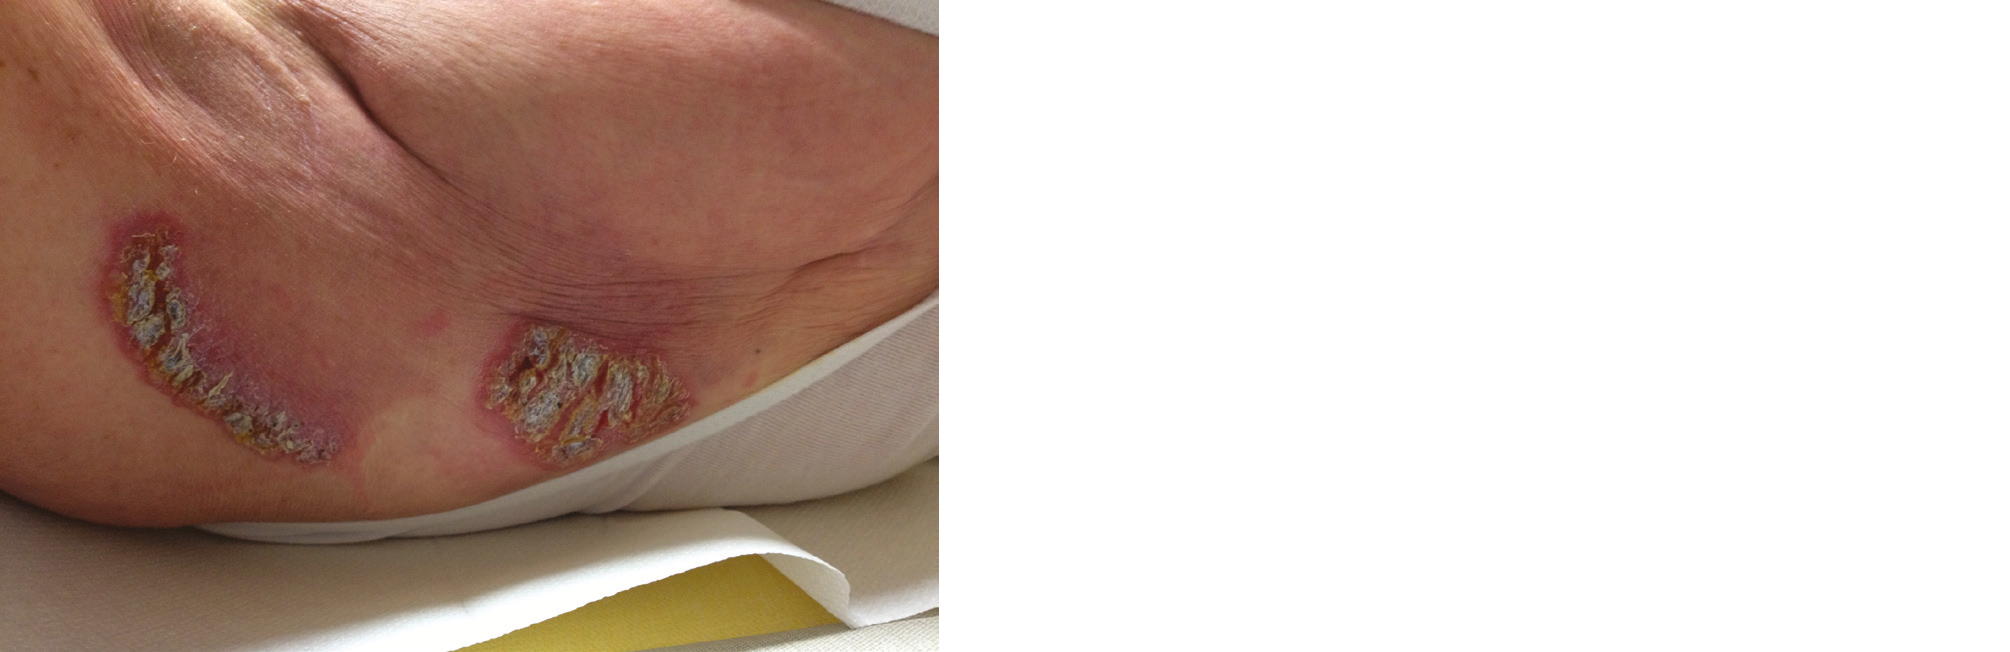

Avant le début du traitement, il convient d'informer le patient sur les risques des réactions et de vérifier la cicatrisation si le patient a été opéré. Un défaut de cicatrisation doit faire reporter le traitement (photo 1). Attention néanmoins à ne pas négliger une poursuite évolutive tumorale locale – empêchant la plaie de se refermer - rare mais possible dans certains cas.

Photo 1 - Retard de cicatrisation post-opératoire